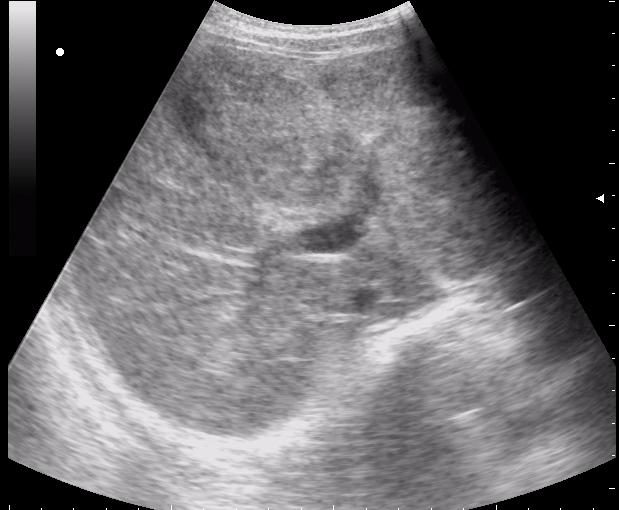

наезд большой черной Прады на маленькую (13кг) 5-летнюю девочку.

получает Медаксон, рабочая версия - изменение желчного пузыря вследствии травмы (шепотом - рекомендация хирургу сменить антибиотик)